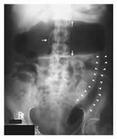

气钡灌肠双重对比造影也是一项有助诊断的检查,特别有助于确定病变范围和严重程度。在钡灌造影中可见到结肠袋形消失,肠壁不规则,假息肉形成以及肠腔变细、僵直。虽然钡灌检查是有价值的,但检查时应谨慎,避免肠道清洁准备,因为它可使结肠炎恶化。无腹泻的病例检查前给3d流汁饮食即可。有腹部征象的病例忌作钡剂灌肠检查,而应作腹部X线平片观察有无中毒性巨结肠、结肠扩张以及膈下游离气体征象。